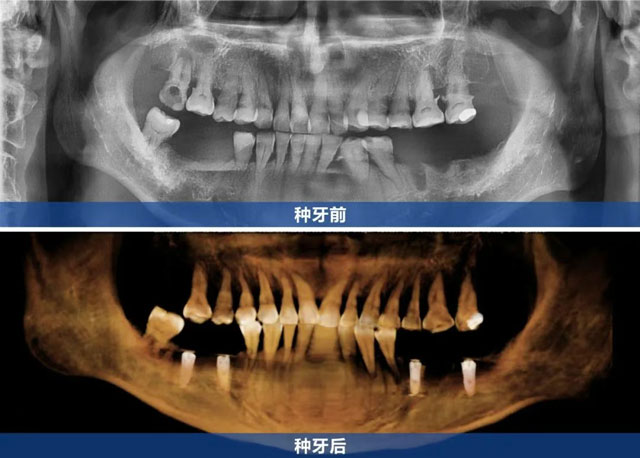

新橋口腔自貢院區的林麗醫生接診后,以專業嚴謹的態度為劉叔叔進行了全面細致的檢查。通過CBCT檢查、口內檢查及詳細問診,林麗醫生明確了劉叔叔的缺牙情況,為其定制了多顆種植修復方案,計劃通過4顆種植牙幫助劉叔叔重建咀嚼功能。

決定手術當天,由新橋口腔成都總院種植專科主任吳建方接診。吳建方主任在獲取劉叔叔之前的情況以及詳細體檢報告后,進行了全面綜合評估,確認其身體狀況能夠接受手術。手術在劉叔叔家人的陪伴下順利完成。術后,他難掩激動之情:“原來種牙這么舒適,我根本不用操心,醫護人員領著我檢查,醫生做手術我都沒什么感覺。”

經過幾次復查,劉叔叔現在狀況穩定,無明顯不適,下一步就可以佩戴牙冠,恢復正常的飲食。他感慨道:“是新橋的服務讓我消除了對手術的恐懼,從看診到手術再到術后貼心的回訪指導,溫暖都在這些細節里,我非常感謝,也期待暢享美食的那一天。”在就診過程中,劉叔叔多次想通過送禮、請吃飯表達謝意,但都被林麗醫生團隊及新橋口腔的醫護人員婉拒。在他們看來,這只是日常工作中眾多成功案例之一。